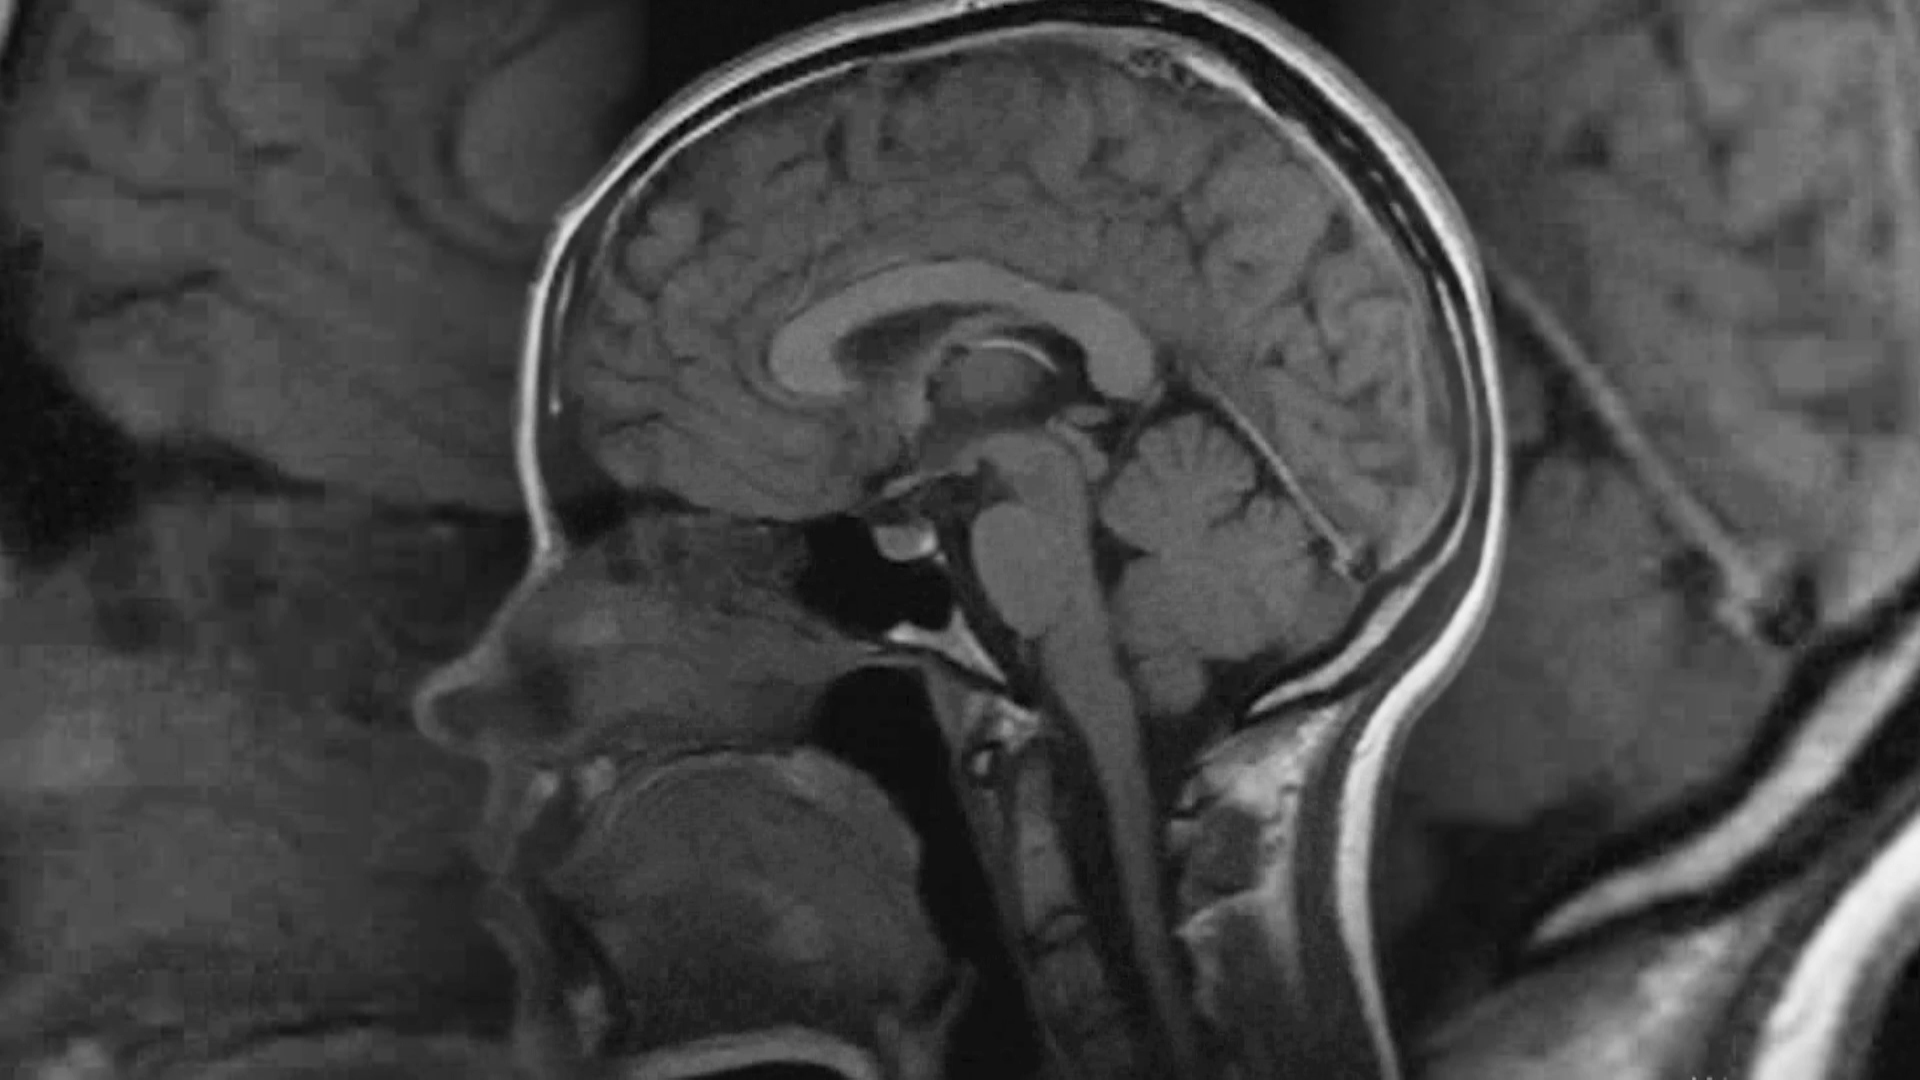

Сериал: EXперименты с Антоном Войцеховским

Антон Войцеховский раскрывает зрителям суть природных явлений и научных открытий, проводит множество опытов не только на высокотехнологичных установках, но и в домашних условиях. Доступный и простой рассказ о том, как устроен мир, ну, или хотя бы отдельные его элементы.

ВедущийАнтон Войцеховский